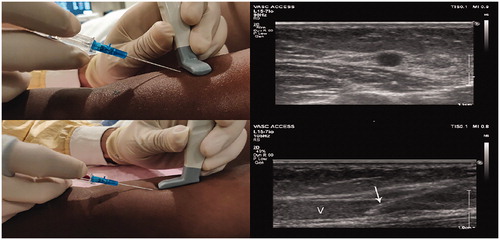

健康なボランティアの右腕のエコーガイドスキャンを行う際の位置を示しています

プローブの向きは、直前に針の先端の可視化の前に、皮膚穿刺直後に対応する超音波画像と針に相対する。